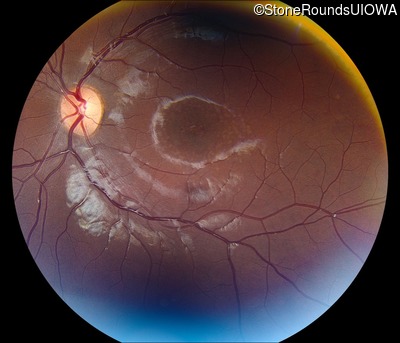

AR Stargardt Disease (IIA)

AR Stargardt Disease (IIA)

This 11 year old female first had difficulty seeing the blackboard at age 8. Later, she developed some photophobia.

Diagnosis & molecular findings

| Disease | Gene | Allele 1 variant(s) | Allele 2 variant(s) | Inheritance mode |

|---|---|---|---|---|

| AR Stargardt Disease | ABCA4 | Gly1961Glu GGA>GAA, Arg212Cys CGC>TGC | Gly1961Glu GGA>GAA, Arg212Cys CGC>TGC | AR |